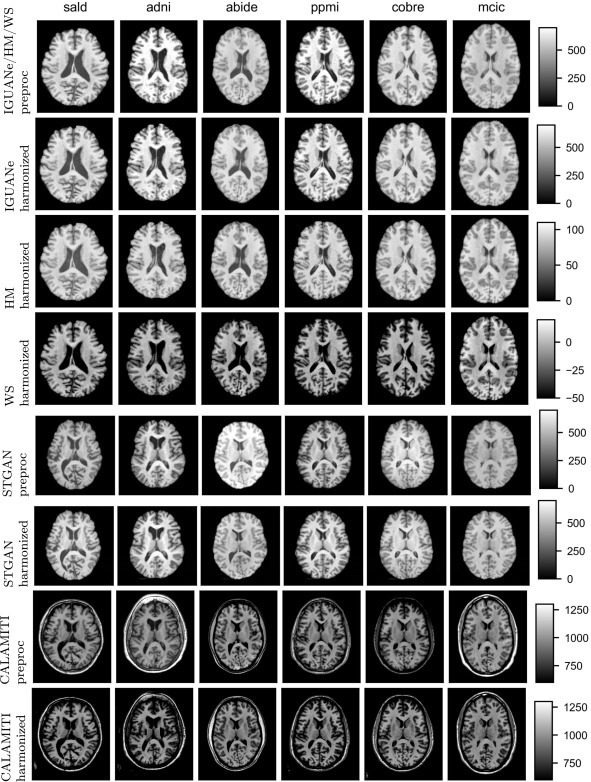

图 G.1. 使用不同协调方法处理后的MR图像可视化。随机抽取来自参考域(SALD)和泛化数据集中的每个研究的一张图像,并显示其中间轴位切片。preproc指对应协调方法预处理后的图像。